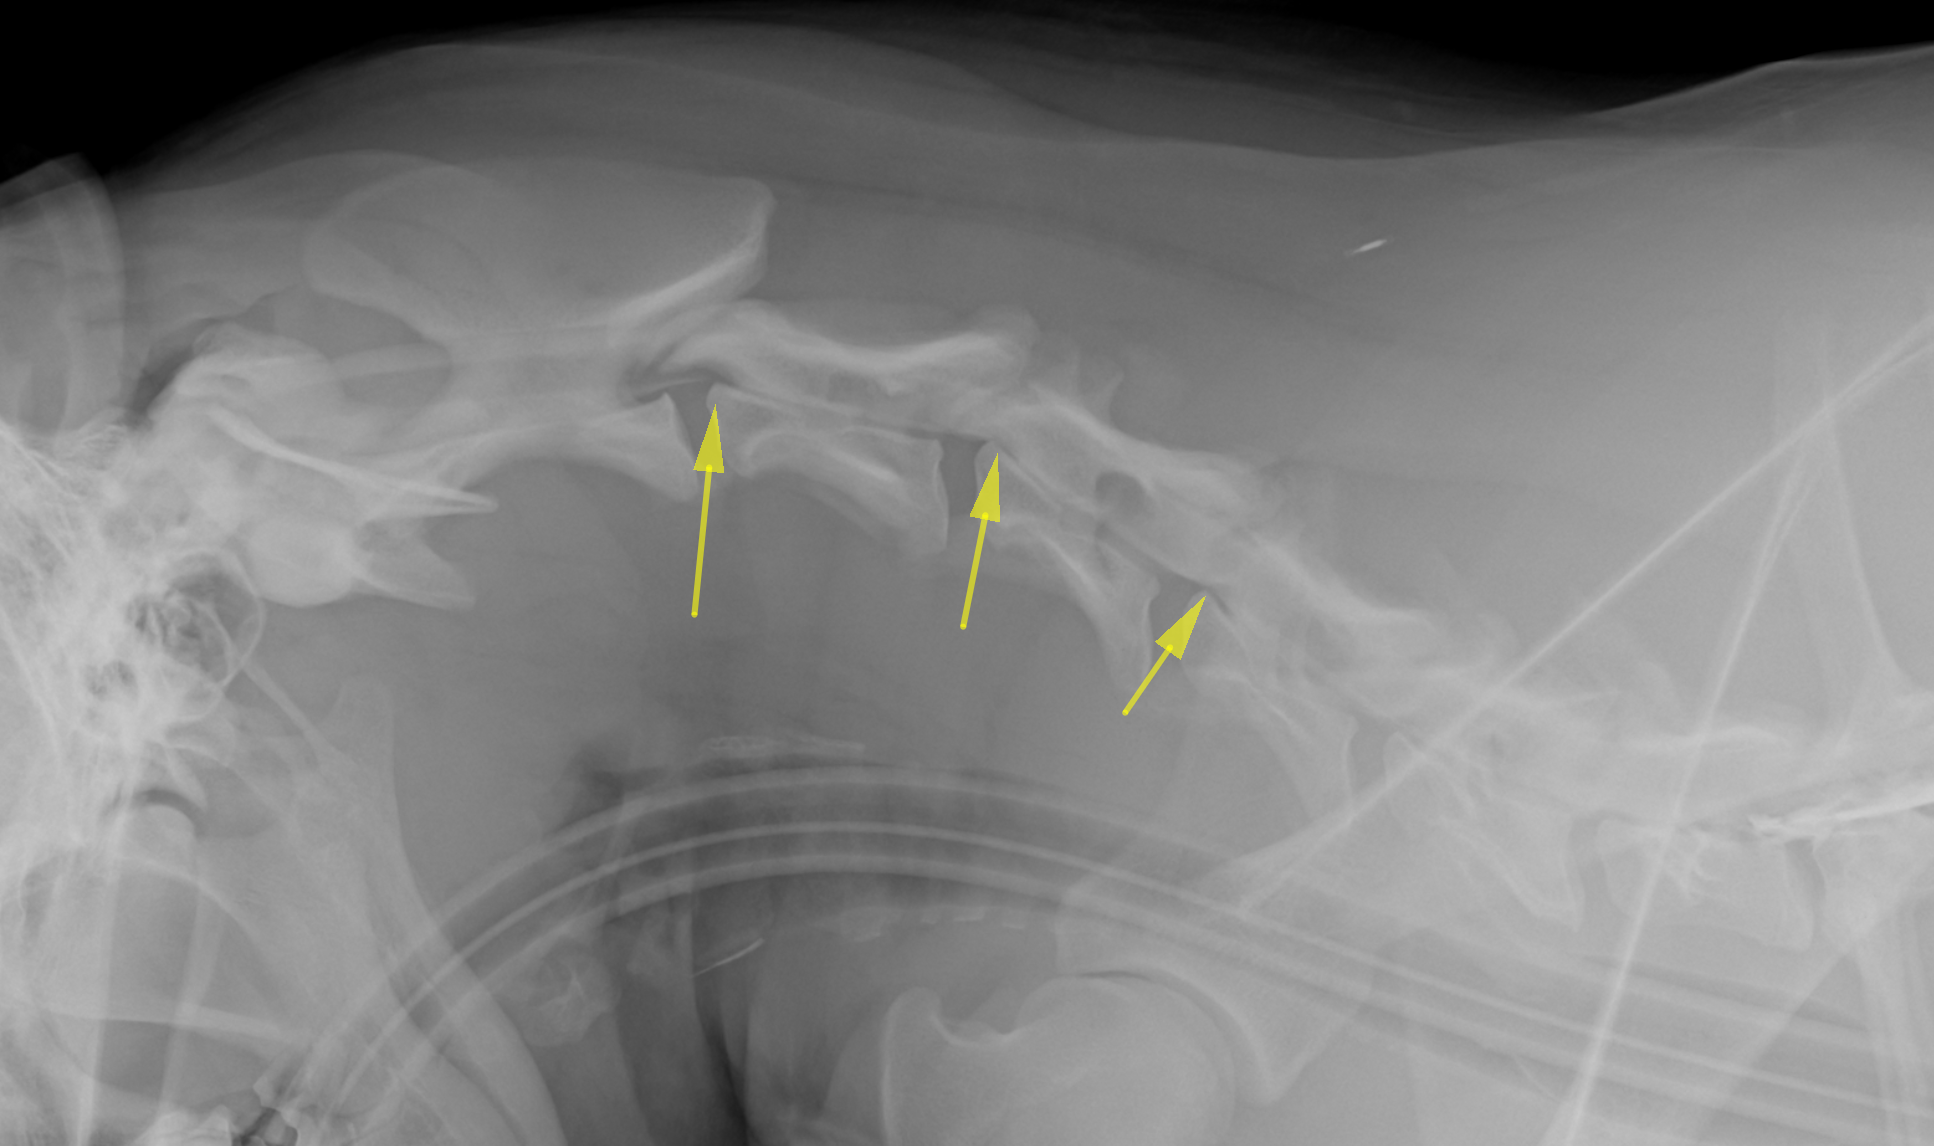

造影X線画像検査です。矢印の部位では首を曲げたときに圧迫が確認されました。